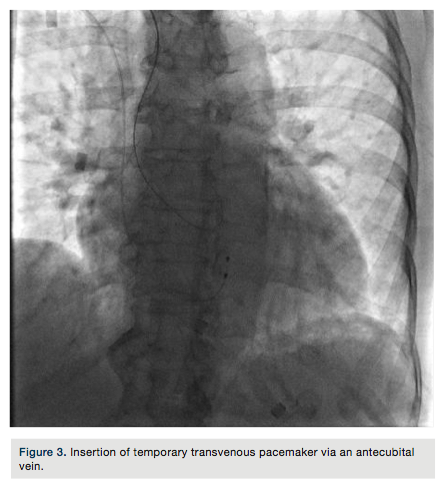

An 84-year-old female with a history of hypertension, diabetes, and dyslipidemia presented to the emergency department with approximately one hour of chest pain and dizziness. Initial electrocardiogram (EKG) demonstrated ST elevations with complete heart block (Figure 1). She was brought to the lab for emergent cardiac catheterization. Diagnostic angiography and percutaneous coronary intervention (PCI) were performed via the right radial artery. A transvenous pacemaker was inserted from the right antecubital vein.

The right radial artery was prepped and draped in sterile fashion, then accessed with a 6 French (Fr) Glidesheath (Terumo). The right antecubital vein was accessed by the nurse prior to the patient’s arrival to the lab and changed (after sterile prep followed by betadine solution) to a 5 Fr Glidesheath (Figure 2). The transvenous pacemaker was advanced  into the right ventricle (Figure 3). Following placement of the pacemaker and capture, a Judkins right (JR) 4 6 Fr guide was used to engage the right coronary artery. Angiography demonstrated a proximal right coronary artery occlusion with TIMI-0 flow (Figure 4). After administration of bivalirudin (Angiomax, The Medicines Company), a Runthrough wire (Terumo) was passed distally. A 1.0 x 10 mm ClearWay balloon (Atrium Medical) was advanced to the lesion and intracoronary abciximab (ReoPro, Eli Lilly & Co.) was administered. Following drug administration, there was improved flow and evidence of a more focal obstruction (Figure 5). A 3.0 x 15 mm Integrity bare metal stent (Medtronic) was deployed at 11 atm with no angiographic residual stenosis and restoration of TIMI-3 flow (Figure 6).  Following revascularization of the right coronary artery, the guide was advanced into the left ventricle to calculate the left ventricular end diastolic pressure (LVEDP) and perform ventriculography (estimated ejection fraction was 55% with mild inferobasal hypokinesis noted on hand injection.  No significant transvalvular gradient was noted on pull-back). A diagnostic Judkins left (JL) 3.5 catheter was then used to engage the left coronary system. Angiography revealed a 90% proximal left anterior descending coronary artery (LAD) stenosis and intermediate disease of the circumflex (Figure 7).  The patient was started on ticagrelor (Brilinta, AstraZeneca) and aspirin, and transferred to the unit. The pacemaker was removed after the patient regained sinus rhythm. She was discharged home after 48 hours with plans for staged intervention of the LAD.